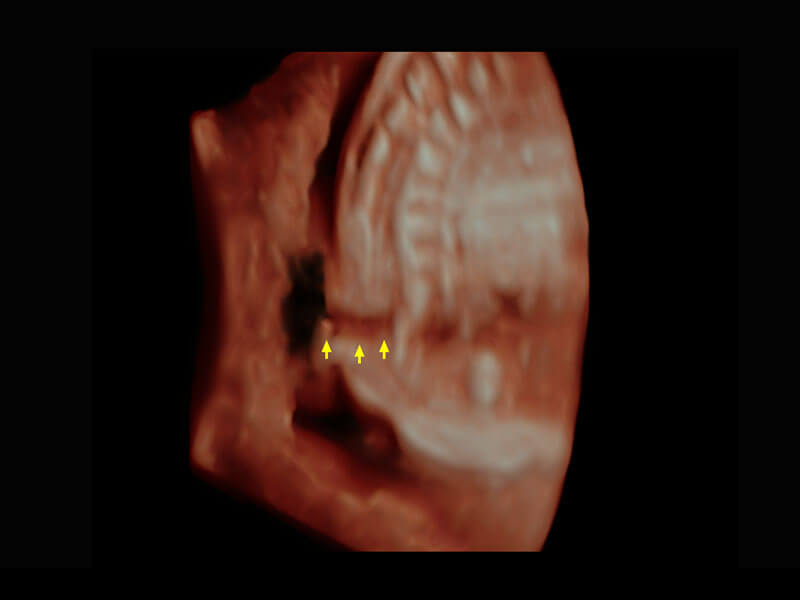

盆底超声

P60为盆底超声检查提供应用方案,多种腔内及腹部容积探头提供从二维、三维到四维的优异图像品质,实时快速三维容积数据获取,专业的测量工具包等人性化设计,为超声医生诊断提供有力保障。

Lev.Hiat A-r: 16.33 cm2

Lev.Hiat H-r: 53.70 mm

Lev.Hiat W-r: 43.96 mm

Lt-LUG-r: 24.16 mm

Rt-LUG-r: 19.94 mm

S-Pelvic

能够简化盆底检查的操作流程,可在二维模式及三维成像模式下实现一键自动提取出标准切面、自动识别当前切面、自动测量,提升盆底检查的高效性,同时也能让青年医生快捷的获得准确的检查结果。